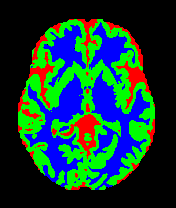

• OASIS-1 [34]: Derived from the Open Access Series of Imaging Studies, this dataset comprises T1-weighted MRI scans from 421 subjects (aged 18–96). The images were acquired with a resolution of 176×208176\times 208 pixels and a slice thickness of 1.25 mm (TR=9.79.7 ms, TE=4.04.0 ms, TI=2020 ms). Following standard protocols, we utilize the provided manual segmentation masks for Cerebrospinal Fluid (CSF), Grey Matter (GM), and White Matter (WM).

• MRBrainS13 [35]: From the MICCAI 2013 challenge, this dataset contains multi-sequence scans of 20 subjects acquired on a 3.0T Philips Achieva scanner. It provides T1 (TR: 7.97.9 ms, TE: 4.54.5 ms), T1-IR, and T2-FLAIR sequences. All scans are co-registered and bias-corrected with a voxel spacing of 0.96×0.96×3.000.96\times 0.96\times 3.00 mm. We utilize the provided labels for CSF, GM, and WM segmentation.

7 Qualitative Evaluation

Fig. 8 and Fig. 10 provide qualitative comparisons on the OASIS-1 and MRBrainS13 datasets, respectively. It is visually evident that the baseline predictions (c) and standard augmentations (e.g., (d), (g), (i)) frequently suffer from noisy artifacts, blurred boundaries, and mis-segmentation of intricate anatomical structures. In stark contrast, our ”Ours+” enhanced methods (e.g., (e), (h), (k)) consistently produce segmentation maps that are visibly cleaner, more spatially coherent, and demonstrate significantly sharper adherence to the Ground Truth (b). This superior fidelity is particularly noticeable in the complex sulcal patterns and holds true across all three backbones (rows), confirming that our framework yields more robust and anatomically plausible results.